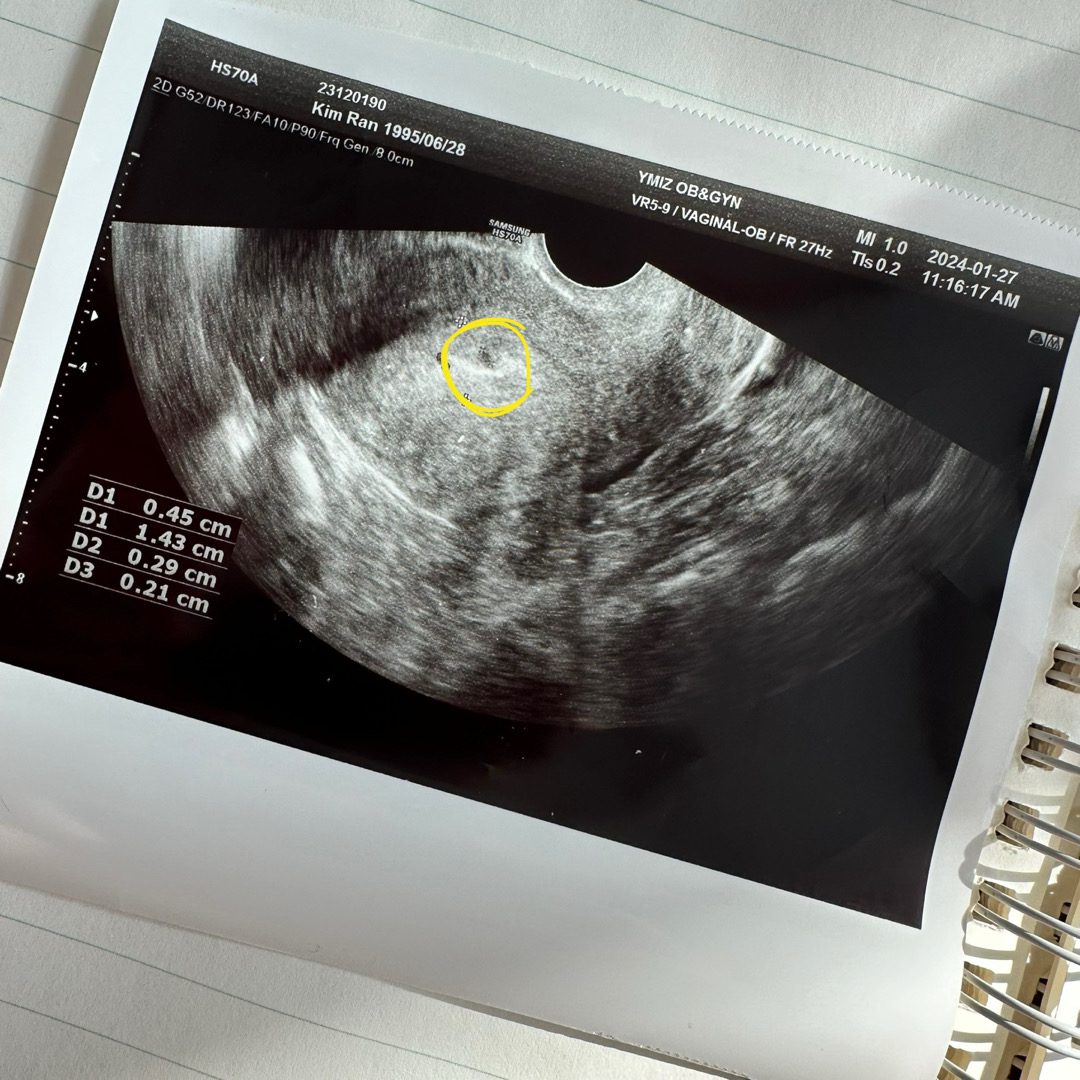

오늘 촘파보러갓다왓어요ㅠㅠ 아기집추정인데 피고임같기도 하다고 다음주 월요일에 다시 보러가기로햇네요..ㅠㅠ 어트케 보이시나요?

저하고 똑같네요 ㅠ 생각보다너무적다고 저두담주월요일에다시보자고하네요